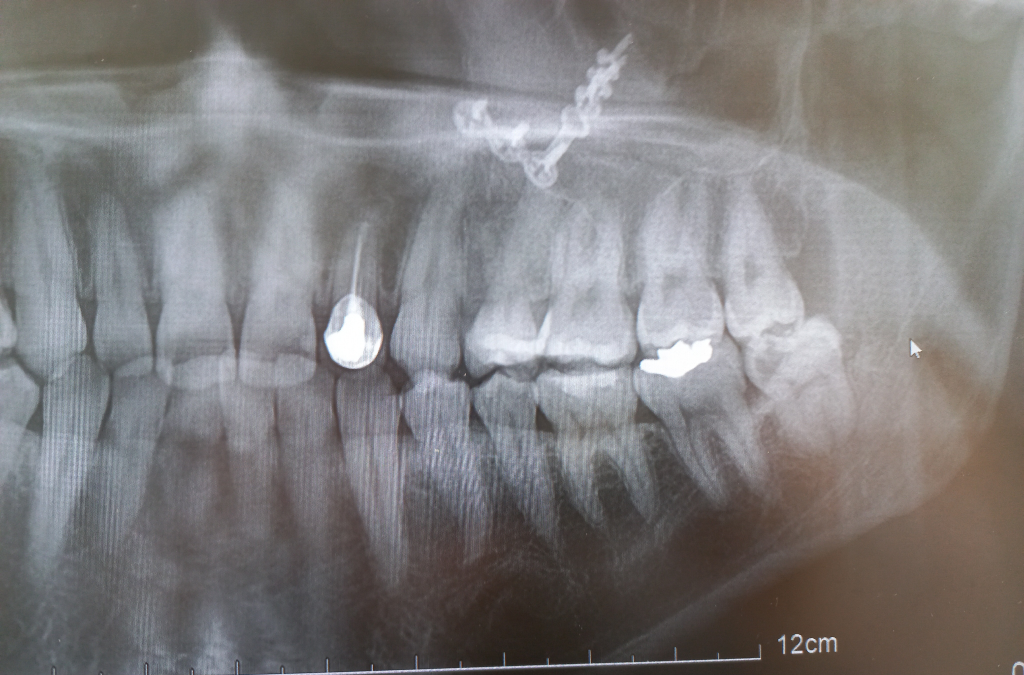

사이충치 인레이나 크라운 치료 한다는데 비용적절한가요?

4. 주어진 파노라마 방사선 사진으로 봐서도 5번은 충치가 많이 진행되었고 6번도 어느정도 충치가 있는 것으로 보입니다.